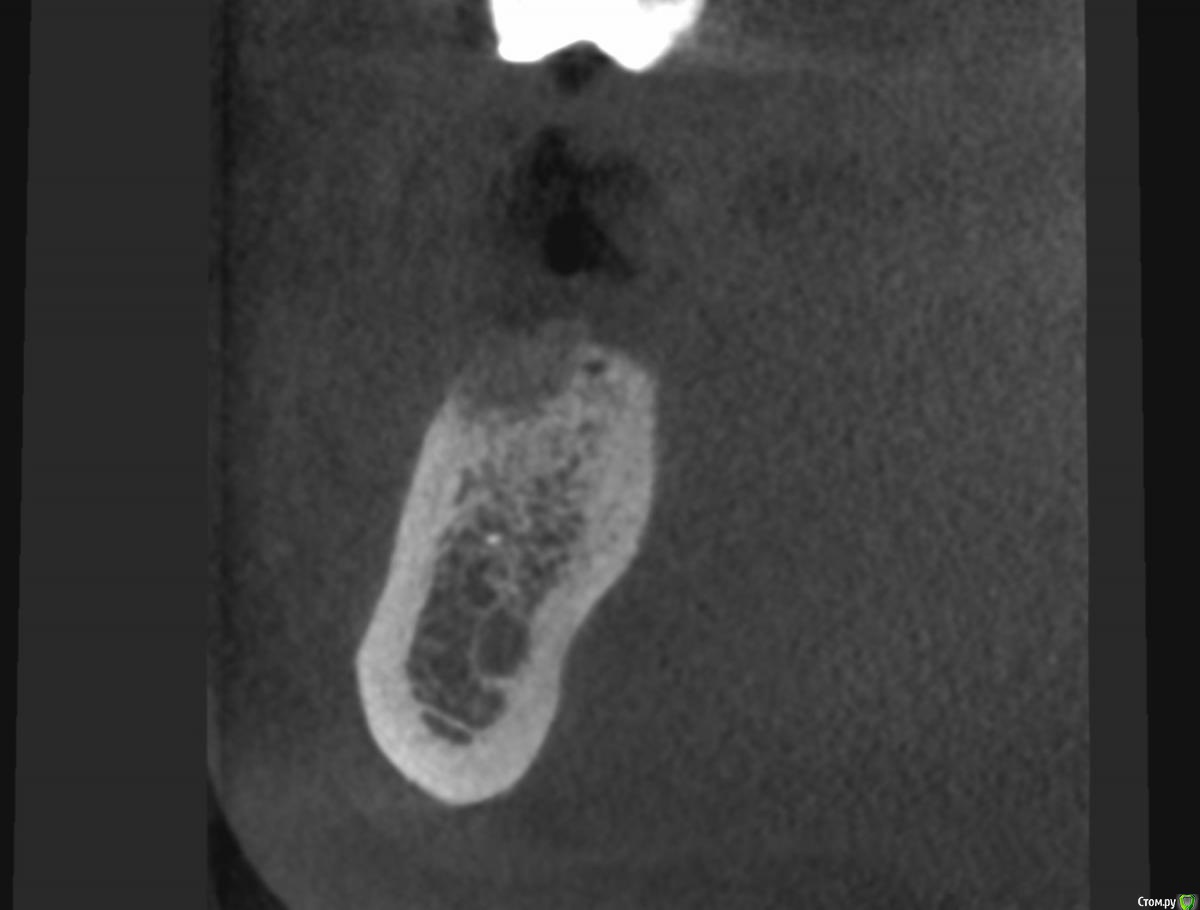

Valerkaa Опубликовано 21 июня, 2019 Поделиться Опубликовано 21 июня, 2019 (изменено) dentikl, извините, что влезаю в вашу тему, не хочу создавать похожую) коллеги, посоветуйте, пожалуйста, к чему готовиться. После удаления прошло 3 месяца (удаление было вне обострения, корни в слизистой практически были). Это грануляции скорее всего? раскрыться, кюретаж и подождать? Сколько ждать по времени? Заранее спасибо. Изменено 21 июня, 2019 пользователем Valerkaa 1 Ссылка на комментарий